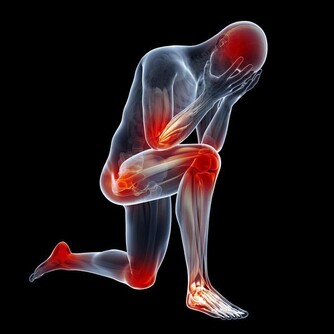

異位性皮膚炎是一種慢性且反覆發作的皮膚疾病,患者常面臨皮膚乾燥、紅腫、劇烈搔癢的困擾,甚至影響日常生活與睡眠品質。然而,許多人發現即使積極治療,異位性皮膚炎仍無法痊癒,反覆發作的情況令人挫折。究竟異位性皮膚炎為何久治不癒?又該如何有效改善?本文將深入探討其成因與解決方法,幫助患者找到緩解之道。

異位性皮膚炎患者的皮膚屏障功能較差,無法有效鎖住水分,導致皮膚乾燥、裂開,甚至讓細菌或病毒趁機侵入,引發發炎反應。此外,頻繁搔抓皮膚會進一步破壞皮膚屏障,使病情加重,形成惡性循環。若未做好適當的皮膚保養,皮膚屏障受損問題將難以恢復,導致異位性皮膚炎持續發作。